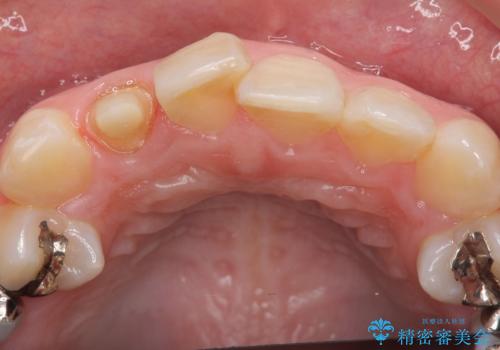

- 右上2番目の歯の被せ物と歯茎の間の継ぎ目が気になるといらっしゃった方の症例です。

再根管治療は希望されなかったため、クラウン除去後、オールセラミッククラウン(スペシャル)による補綴を行いました。